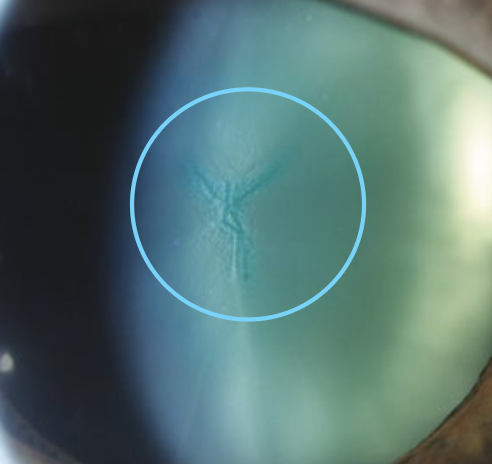

What are epicapsular stars?

Normal but uncommon variant

Starfish-shaped melanocytes can be seen on the anterior lens capsule